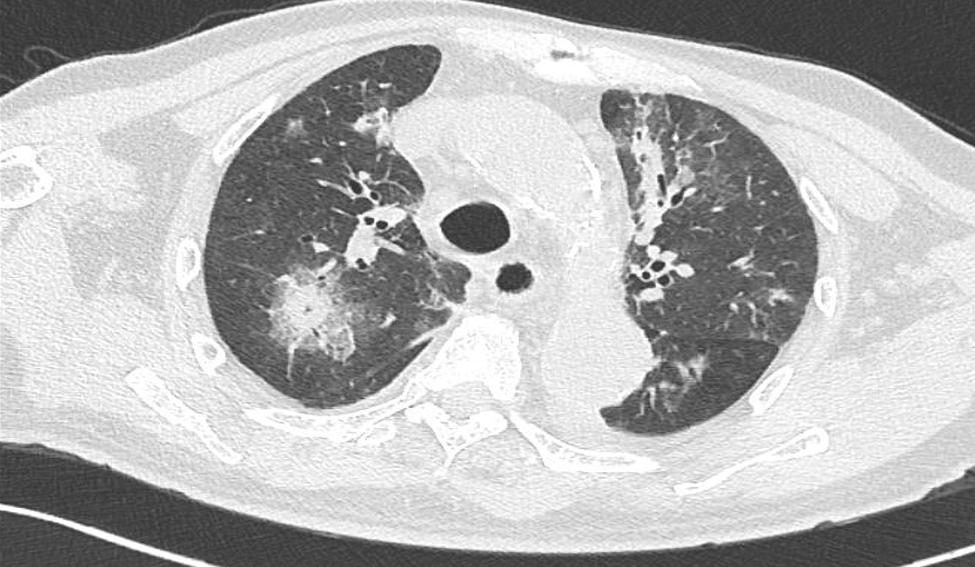

入院进行查体,双肺可闻及散在湿性啰音,未闻及明显干性啰音及胸膜摩擦音;心界无扩大,心率88次/分,心律绝对不齐,第一心音强弱不等;脐下腹正中线处可见一长约10cm陈旧性手术疤痕。 肺部CT显示双肺多发炎症 (图1)。辅助检查显示中性细胞、淋巴细胞、血小板、C反应蛋白等数据存在异常(图2)。故 初步诊断为新型冠状病毒感染(中型)、高血压病3级(极高危)、高血压性心脏病、冠状动脉粥样硬化性心脏病、心房颤动、乙状结肠癌根治术后和痛风性关节炎。

图1